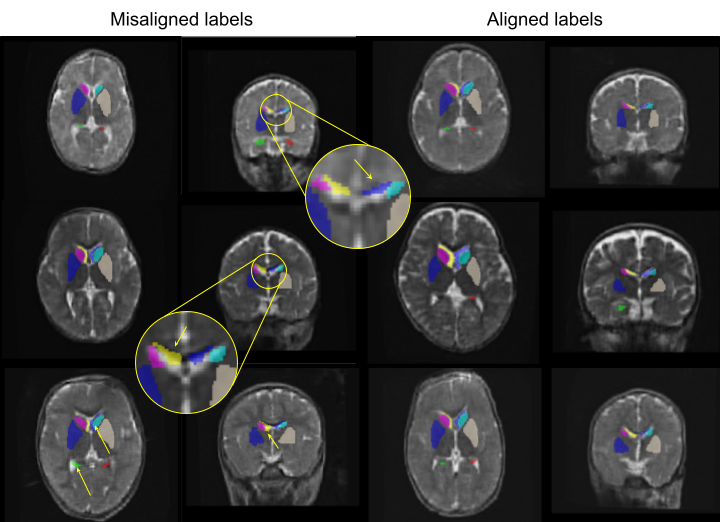

We provide here a more detailed outlook at our manual quality assessment. We carried out a visual qualitative assessment of label alignment across all available data, focusing around the coronal view of the images, using ITK-Snap. As illustrated in Figure S1, the coronal view revealed several subjects with the caudate and ventricles being shifted. This is particularly visible in the zoomed-in subjects, where the left hemisphere ventricle (first row) and the right hemisphere ventricle (second row) are shifted and do not cover the ventricle (bright tissue on the image). These data were subsequently excluded from training, resulting in the discarding of 23 our of 79 data points. The complete manual rating is available at https://github.com/Medical-Image-Analysis-Laboratory/lisasegm/blob/main/LISA_QC.csv.

Across most experiments, FT‑Real models (trained on synthetic data and then fine‑tuned on real high‑field images) consistently outperformed those trained on synthetic data alone. Despite the HF–ULF domain shift, the models benefited from additional T2 information in the HF data. Having never seen the LISA data, these models were not competitive quantitatively, but BOBs-based models still yielded qualitatively good segmentations, especially in the ventricles and caudate nuclei, as illustrated in Figure 3. This figure also helped us realize that some of the ground truth annotations were misregistered (see yellow arrows on the left side of the image). We also observed that the segmentations produced by our pre‑trained models were well aligned in these cases.

A manual inspection of the provided training dataset revealed that the HF annotations had some misalignment around the right hemisphere ventricle and caudate in at least 23 out of 79 training cases, similar to those errors depicted in the figure 3 A. On Figure 3 B, the Dice score computed on these structures using our pre-trained models and the ground truth LISA labels did show a correlation between a lower Dice score and data that we rated as misaligned. A more detailed explanation of our manual label quality rating is provided in Appendix S1.